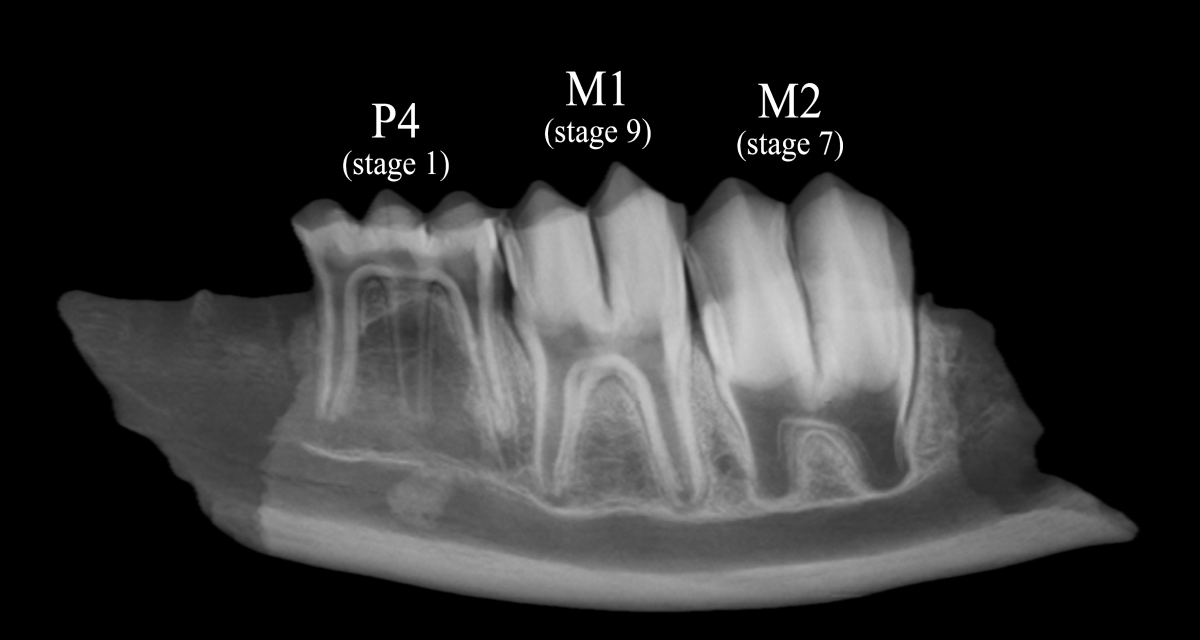

分析では、出土したニホンジカ下顎骨をX線撮影して、歯の成長段階から死亡時の月齢を算出しました。 一般に動物の歯は、比較的短い時間の中で規則的に成長します。そのため、歯がどれくらい成長しているかを細かく観察すると、生まれてからの月齢を知ることができます。そして、その月齢を生態学に基づくニホンジカの出生日にあてはめることで、出土したシカがどの季節に死んだのか、すなわち縄文人によって捕獲された季節を推定していきました。

図 ニホンジカ下顎骨のX線画像 歯の成長の様子から、このシカは約11ヶ月齢で、5月前半に死亡したと考えられる。